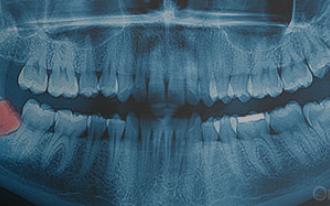

Nem todos os dentes do siso estão totalmente à superfície.

Em vez de nascerem completamente, os dentes do siso podem ficar inclusos, o que implica uma diferente abordagem clínica, no processo de extração.

Extração dos dentes do siso.

É preciso extrair os dentes do siso? A idade tem importância?

Os dentes do siso são os últimos dentes a nascer e devem ser cuidadosamente analisados pelo médico dentista.

Dente incluso: como é extraído?

Dentes inclusos: como são extraídos?

Alguns dentes do siso podem ser considerados dentes inclusos.